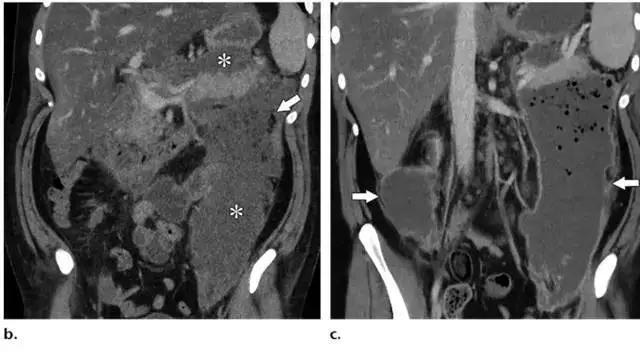

同时受累的亚型:表现为胰腺及胰周无强化坏死物,多累及小网膜囊和肾前间隙(图 3a)。

胰周型:表现为胰腺强化正常,而胰周坏死,坏死物可包括不等量的液体和和非液性成分,约占坏死性胰腺炎的 20%(图 3b)。

胰腺型:仅占 5%,没有胰周坏死物。在发病的前几天胰腺可仅表现为水肿,局限或弥漫性低强化,可能很难与 IEP 相鉴别,在这些病例中,在发病 5~7 天后再次行 CT 增强扫描可以提高诊断坏死性胰腺炎的准确率。

图 3 坏死性胰腺炎亚型在增强轴位 CT 的表现。a 胰腺和胰周同时受累的 58 岁女性患者,胰体无强化(*),正常强化的胰尾(黑箭头),小网膜囊内 ANC(白箭头)。b 仅胰周受累的 18 岁男性患者,可见一周为大片不均质密度(箭头),和 ANC 相符。胰腺实质密度正常(*)。c 仅胰腺实质受累的 33 岁男性患者,可见大片局限无强化的胰腺实质和脂肪密度(*),诊断为 WON。仅周边可见少量残余强化的胰腺实质(箭头)